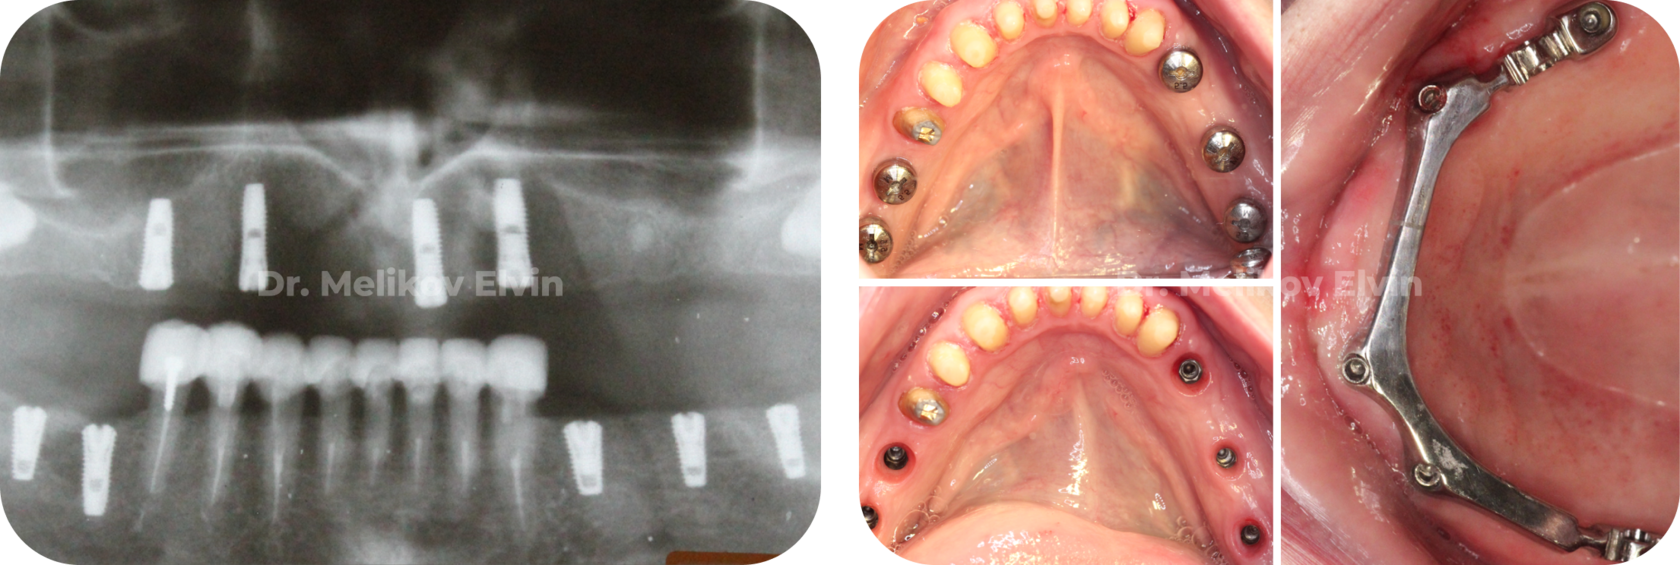

Произведена установка 9 дентальных имплантатов Dentium.

Челюстно-лицевой хирург, имплантолог: Меликов Эльвин Аббасалиевич.

Этапы имплантации.

После установки дентальных имплантатов на нижней челюсти и на верхней челюсти (балочная конструкция).

Ортопедические коронки на винтовой фиксации для нижней челюсти.